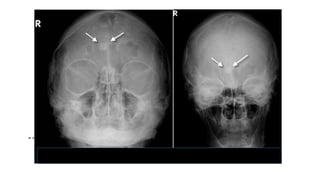

El osteoma clásico se da en el cráneo, senos paranasales y la mandíbula.

Rayos X ; La lesión es circunscrita de extraordinaria densidad, redondeada y

generalmente menor de 2 cm, aunque pueden alcanzar dimensiones enormes.